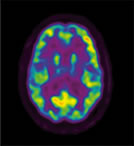

Frontal Lobes

Frontal Lobes Frontal Lobes

Thalamus

Thalamus Thalamus

Neural imaging patterns and EEG research show that TM practice produces a unique state of restful alertness, which can be seen in the decreased activity in the thalamus (the area of the brain that relays input to all other parts of the brain) and increased activity in the frontal and parietal cortices (two areas involved in attention).